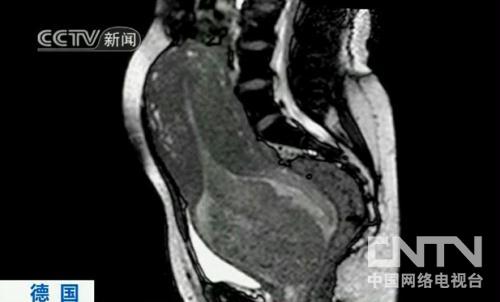

ÖйúÍøÂçµçÊǪ́ÏûÏ¢£ºµÂ¹ú°ØÁÖɳÀïÌØÒ½ÔºµÄÒ½ÉúʵÏÖÁËÒ»ÏîÒ½Ñ§Í»ÆÆ£¬ËûÃÇʹÓú˴ʲÕñ³ÉÏñɨÃèÒÇ»ñµÃÓ¤¶ù³öÉú¹ý³ÌµÄͼÏñ£¬ÕâÔÚÀúÊ·ÉÏ»¹ÊǵÚÒ»´Î¡£ÕâЩͼÏñÊÇÒ»ÃûµÂ¹úÔи¾Í¬ÒâÔں˴ʲÕñ³ÉÏñɨÃèÒÇÄÚÉú²úºóÅÄÉãµÄ£¬Äܹ»°ïÖúÒ½Éú½øÒ»²½Á˽âÉú²ú¹ý³Ì£¬Í¬Ê±Ò²¿ÉÓÃÓÚÕü¾ÈδÀ´µÄÉúÃü¡£